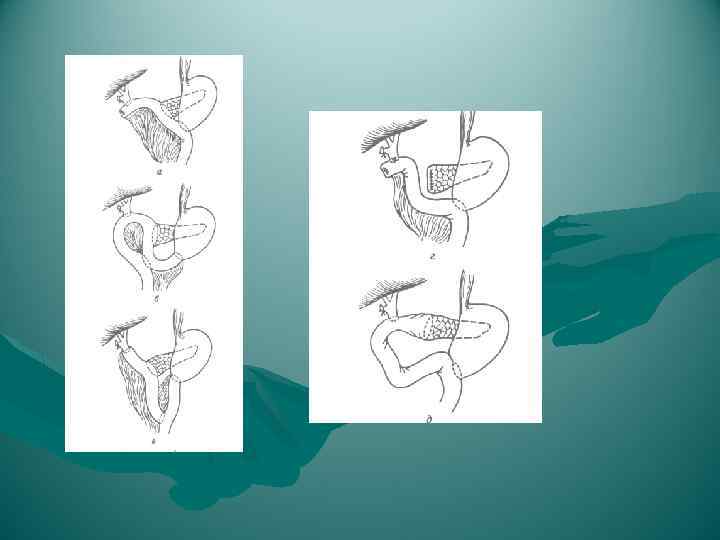

Холецистэктомия от дна

Холецистэктомия от дна

Холецистэктомия от дна

Холецистэктомия от дна

Холецитэктомия от шейки

Холецитэктомия от шейки